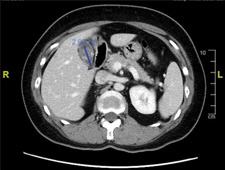

斷層掃描顯示膽結石3公分,塞滿了整個膽囊。